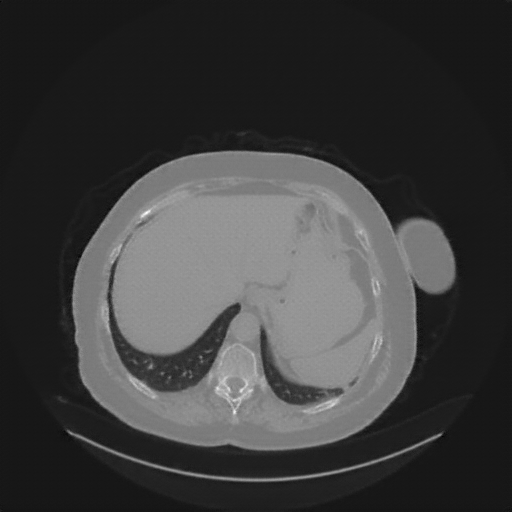

Generated VENOUS CT scan (A→B translation)

No window - Raw intensity values

Lung window (WL -600, WW 1500 β†’ Low βˆ’1350, High +150)

Mediastinum window (WL 40, WW 400 β†’ Low βˆ’160, High +240)